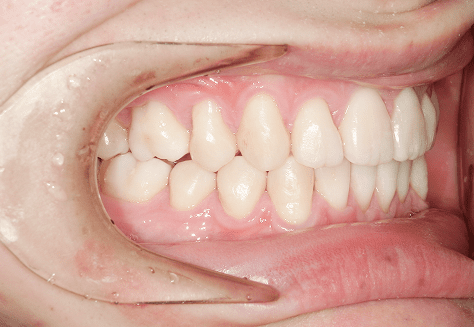

S.K

治療前

治療後

主訴

歯が重なっていて気になる。前歯が出ていて唇が閉じにくい。ハミガキがしにくい。

診断

上顎前突・叢生

年齢/性別

20代/男性

抜歯部位

上下第三大臼歯

使用装置

上下インビザライン

保定装置

上下ビベラリテーナー

料金

初回資料採得・・・・・・・30,000円

診断料・・・・・・・・・・33,000円

動的治療終了時資料採得・・5,500円 -

基本料金

990,000円

診察料金

1,100円×33回

-

治療期間

3年5カ月